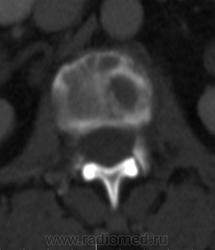

Костное окно:

Я всегда с интересом отношусь к "высоким технологиям", но, как свидетельствуют данные, картинка тел пораженных позвонков при миеломе очень напоминает "картинку мозга"...

По имеющимся файлам-дайком я не нашла признаков опухоли. Имеется множественное остеолитическое поражение позвоночника, ребер, грудины, частично - таза. Лимфоузлы не увеличены. Тоже поставила бы на первое место миеломную болезнь. Диагностирование её не всегда простое дело. Поражена грудина и, наверное, нужно посоветоваться с онкологом (гематологом) стоит ли сделать стернальную пункцию.Советую написать в личку tatyana.